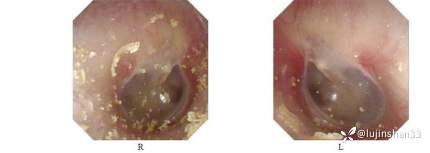

查体:耳:双耳廓无畸形,双侧外耳道通畅,鼓膜完整,标志清楚,未见异常渗出。音叉检查患儿不能配合。